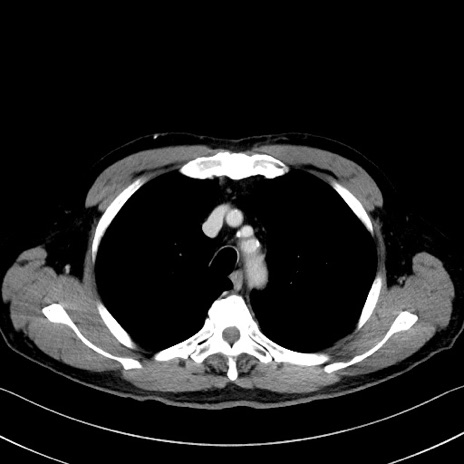

冠状断像